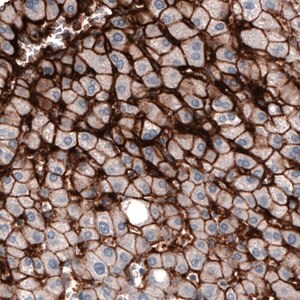

Prestige Antibodies® 라인의 CL3771 클론 단일클론 항체로, 인간 SLCO1B3 단백질을 인식합니다. 정제된 IgG1 형태의 1차 항체이며, 면역조직화학에 적합합니다. −20°C에서 보관하며, 습한 얼음 상태로 배송됩니다.

Prestige Antibodies® Powered by Atlas Antibodies, clone CL3771.

| Technique(s) | Immunohistochemistry (1:500–1:10000) |